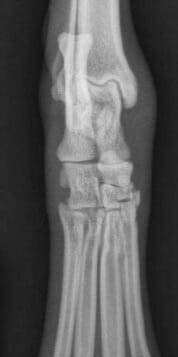

Les lésions ligamentaires s'accompagnent invariablement d'un certain degré d'instabilité de l'articulation. Les lésions musculo-tendineuses sont moins fréquentes et peuvent être plus difficiles à détecter à l'examen clinique, mais une douleur focale évidente et une chaleur et un gonflement marqués sont généralement présents dans les lésions de grade 2 et 3. Il y a souvent des écchymoses spectaculaires et, au début, un défaut physique est palpable à l'endroit de la blessure. En l'absence de traitement, des gonflements importants peuvent apparaître lorsque l'hématome est remplacé par du tissu fibreux (Figure 1).

La radiographie simple peut être utile pour évaluer la présence d'une tuméfaction focale des tissus mous et la radiographie "sous contrainte" peut être utile pour documenter l'instabilité de l'articulation en cas de lésion ligamentaire importante ( Figure 2).